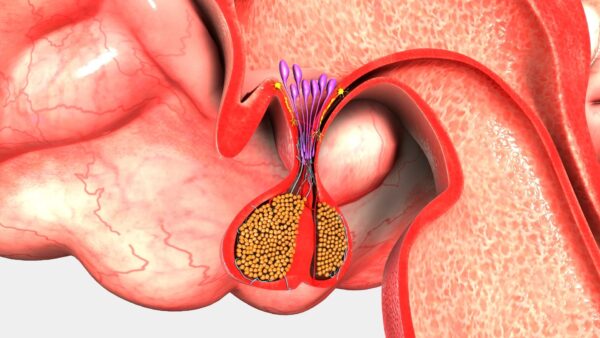

- Hormona luteinizante (LH) y hormona foliculoestimulante (FSH): Son esenciales para la función reproductiva, estimulando la producción de hormonas sexuales y el desarrollo de los órganos reproductores.